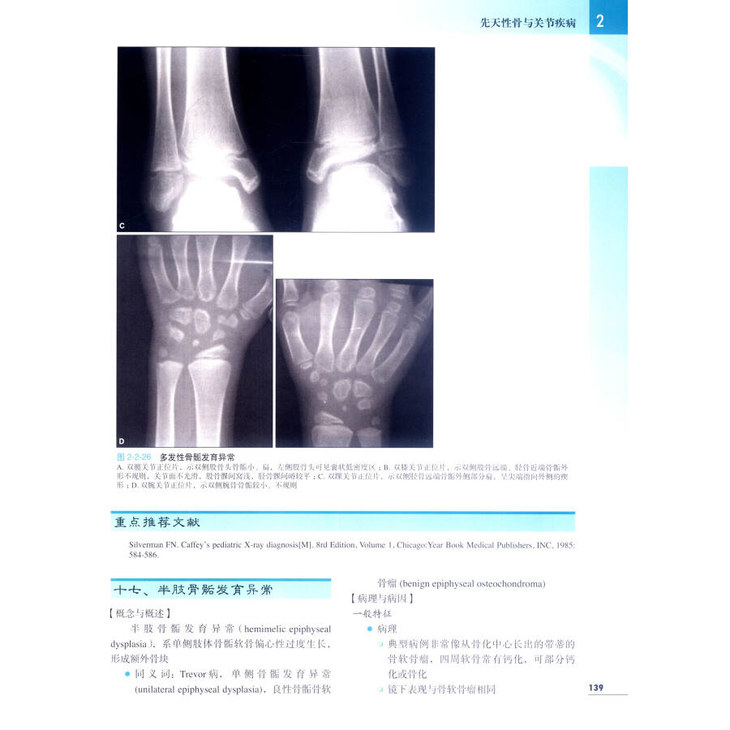

★ 内页插图 ★